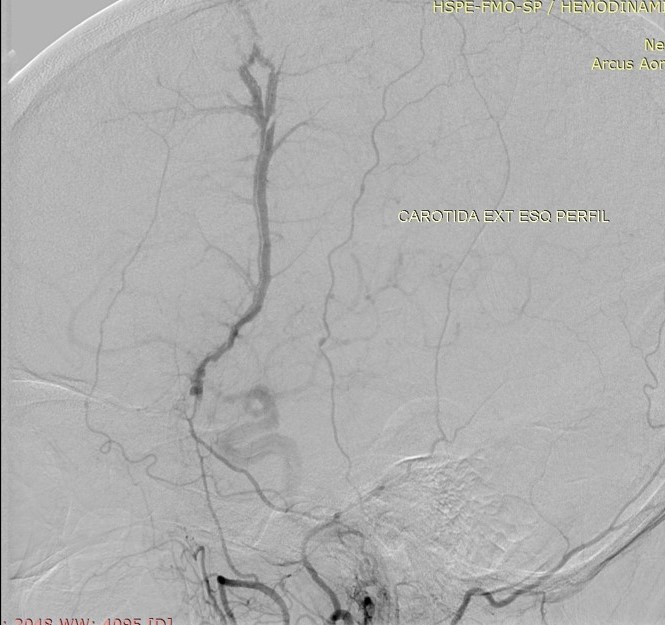

Discussão de tratamento de Fístula Arteriovenosa Dural grau I

Malformações artério venosas durais intracranianas - Discussão de caso fístula dural pós traumática grau I

Em 1995, Cognard et al. analisaram retrospectivamente 205 pacientes portadores de FAVDs, atendidos no período de 18 anos, em três grandes centros de referência no mundo. Algumas alterações e complementações foram propostas à classificação estabelecida anteriormente por Djindjian et al.  Na classificação publicada por Cognard et al., as lesões tipo I possuem drenagem diretamente para o interior de um seiovenoso dural, somente de forma anterógrada . As lesões tipo II são caracterizadas por elevada sobrecarga arterial e insuficiente drenagem venosa anterógrada. Ocorre, então, fluxo retrógrado ao longo do seio venoso.  Essa categoria é subdividida em três grupos,incluindo: tipo lIa com fluxo retrógrado somente no interior do seio venoso; tipo Ilb, com fluxo anterógrado no interior do seio venoso e refluxo para as veias corticais; e tipo lIa + b, com fluxo retrógrado para o seio e veias corticais. As lesões tipo III drenam exclusivamente para as veias corticais sem ectasia venosa. As lesões tipo IV drenam diretamente para as veias corticais que possuem ectasia venosa (dilatação maior que 5 mm de diâmetro). Finalmente, Cognard et al.acrescentaram um novo grupo, representado pelas lesões que drenam diretamente para as veias perimedulares espinhais, classificando-as como tipo V.